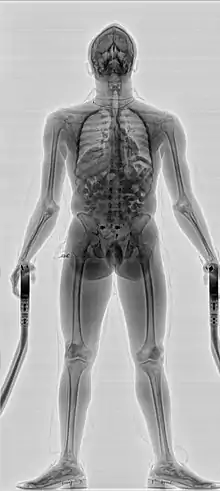

- Сканеры персонального досмотра, основанные на технологии проникающего рентгеновского излучения.[6] В этих сканерах рентгеновское излучение проходит сквозь тело человека и затем улавливается детектором или линейкой детекторов. Этот вид сканеров персонального досмотра позволяет обнаружить объекты, спрятанные не только под одеждой, но и внутри тела человека (например, перевозимые наркокурьерами в желудке наркотики) или в его естественных полостях. Полученная доза составляет в районе 0,25 μSv и в основном регулируется американским стандартом по радиационной безопасности для систем персонального досмотра, использующих гамма или рентгеновское излучение ANSI 43.17.2009[7]. Существуют модификации в рентгенозащитной кабине, позволяющей исключить воздействие отражённого излучения на персонал и окружающих людей. Можно выделить одно- и двух проекционные сканеры, позволяющие одной проекцией получить снимок всего тела, а второй проекцией получить снимок определённых областей (например, области живота), представляющих интерес с точки зрения поиска сокрытых предметов. Обычно сканирование по второй проекции происходит на большей дозе и является уже не стандартной процедурой, а углублённым досмотром подозрительного субъекта, проводимой выборочно и обычно по подозрению сотрудников служб.